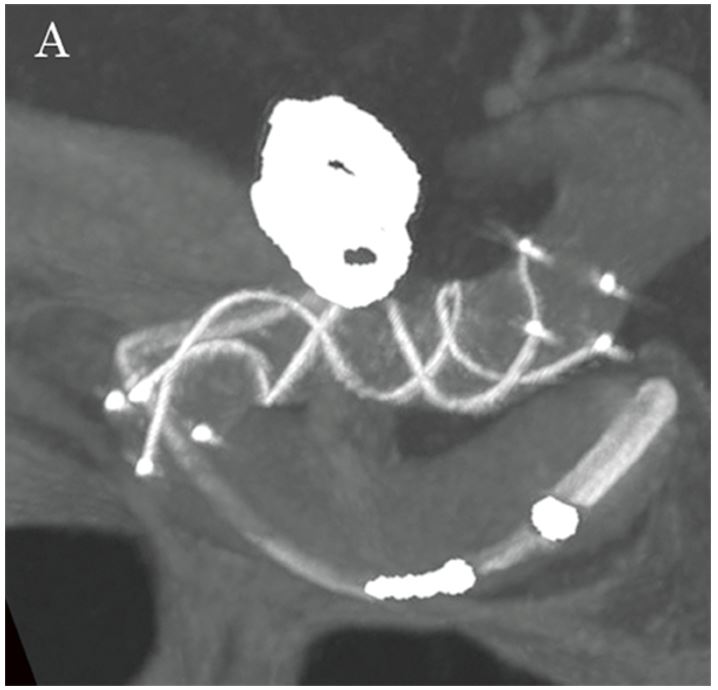

Кут роботи (WA) визначався за допомогою 3D-цифрової субтракційної ангіографії (DSA), для візуалізації нерозірваної аневризми лівої внутрішньої сонної артерії (малюнок 1А).

Флюорографічні зображення, отримані за допомогою Hi-Def Detector, дозволили чітко спостерігати поведінку котушки та мікрокатетера, а також розгортання стенту за допомогою високороздільних зображень, що забезпечило надзвичайно ефективну підтримку під час процедури (малюнки 2A та 2B). Далі, за допомогою опції Alpha CT (конусно-променевої комп'ютерної томографії), було підтверджено стан розгортання стенту та затискування головної судини (малюнки 3А та 3В), після чого проведено додаткову емболізацію з використанням спіральних котушок в зоні втікання до аневризми. Лікування було завершено із щільністю запаковування котушкою у 28,24%. Наявність або відсутність інтранкраніального крововиливу було підтверджено за допомогою Alpha CT.

Малюнок 2A: Флюорографічне зображення, отримане за допомогою Hi-Def детектора (3 дюйми) під час розміщення LVIS.

Малюнок 3A: Alpha CT мультипланарна реконструкція, що показує стент LVIS